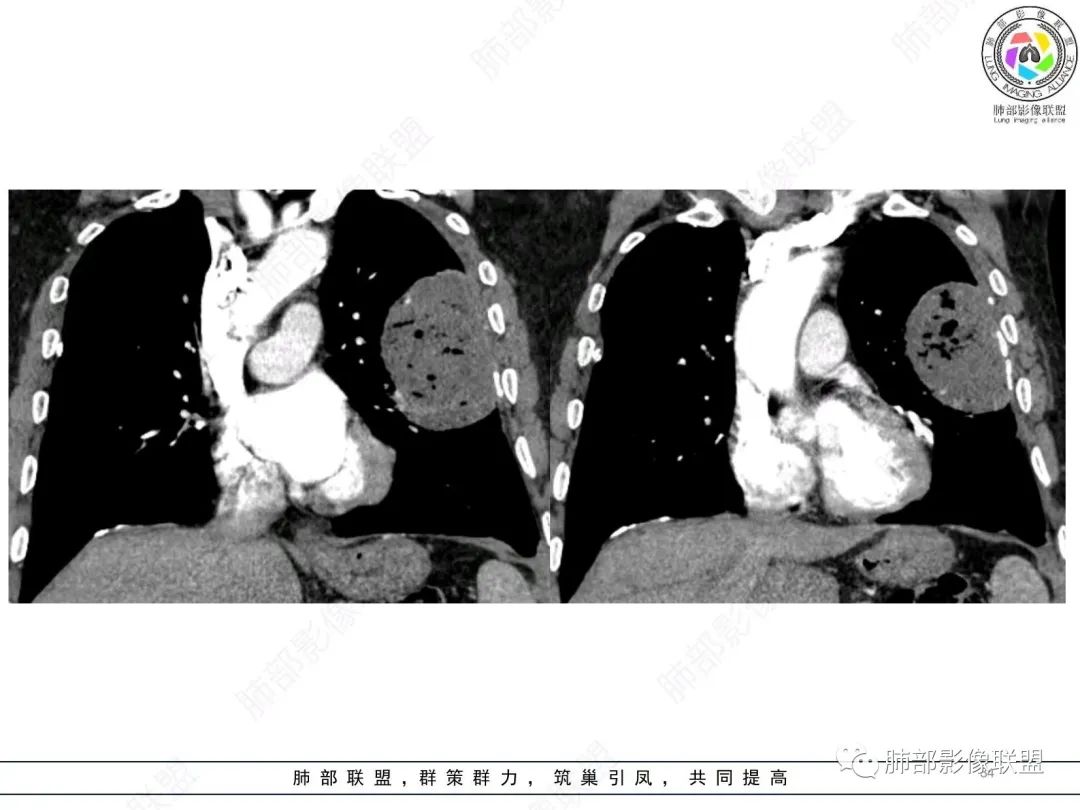

我要修正一下观点了:仔细看了视频,肿块占位效应明显,对周围血管,支气管有推挤,增强后强化不明显,NSE增高,半年体重下降25公斤,虽然有内部支气管扩张,血管漂浮,边界清楚支持淋巴瘤,但强化太低,膨隆,占位推挤太明显(淋巴瘤一般没有这么明显的占位效应),胸膜关系有载桩,恶病质明显(乏力,半年体重下降了25公斤),NSE也明显增高,就不支持淋巴瘤了。还是考虑外朝内的恶性肿瘤,间质来源的肉瘤伴有神经内分泌分化或者大神泌。

不支持淋巴瘤的有四点:1、对周围血管支气管推挤明显。2、胸膜有栽桩,3、强化太弱(淋巴瘤一般还是中度以上甚至高度强化多见),4、NSE升高明显,体重下降太明显。

大肿块,边缘光滑,深分叶

部分类似于脐凹征

大肿块、表面光滑但深分叶,肺门侧支气管堵塞

回头看,内部支气管近端其实不连续,伴随肺动脉不存在